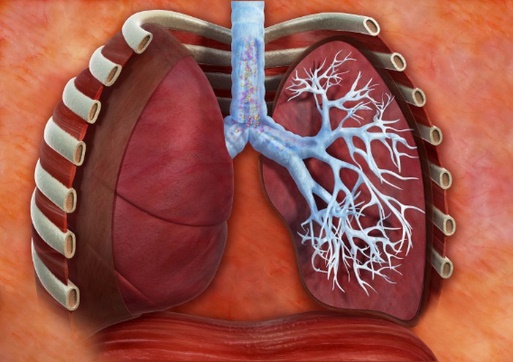

Pnewmokoniozlar

Plewritler

Öýkenleriň tuberkulýomasy

Öýkenleriň ojaklaýyn inçekeseli

Ötüşen tozanly bronhit

Öýkenden daşky inçekesel